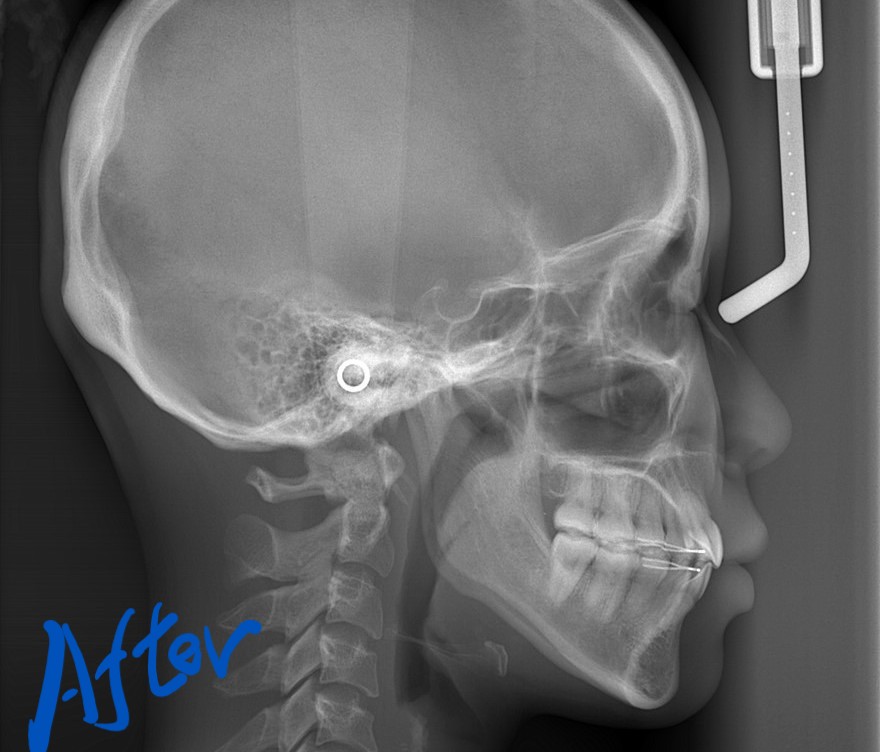

レントゲン写真でも比較してみましょう

左側が矯正治療前、右側が矯正治療後